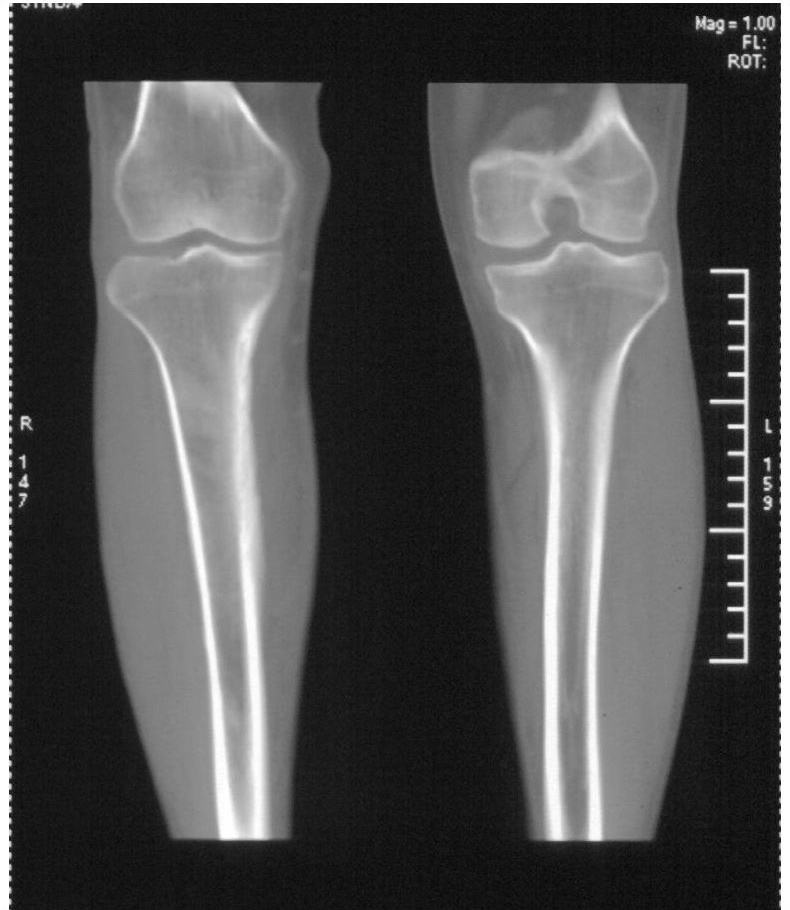

该患者到某三级医院进行会诊,并重新作了平片检查,认为畸形性行骨炎: